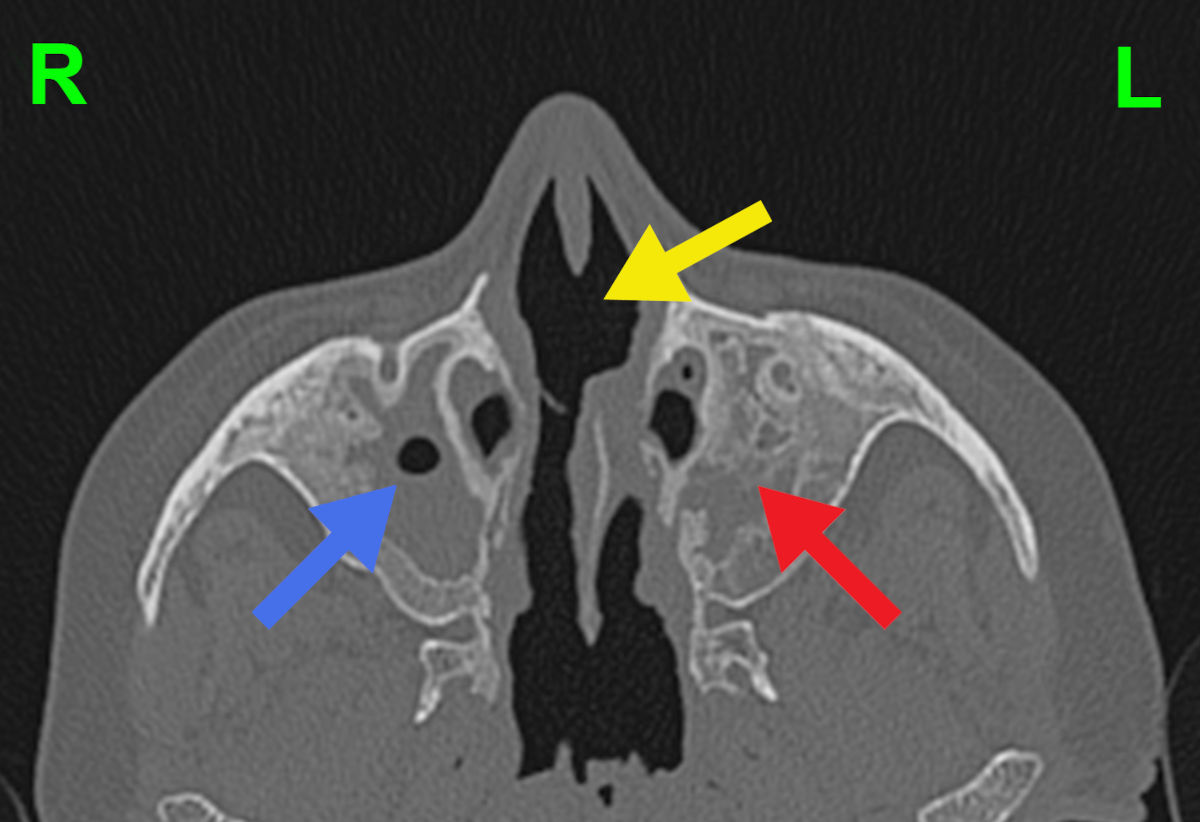

CT and MRI scans showed no aeration of the paranasal sinuses, foci of bone destruction and a significant amount of scar tissue. The anatomy of the nasal cavity was completely disturbed (Fig. 4-5).

Figure 4. Axial CT scan shows residual aeration of the right maxillary sinus (blue arrow), bone destruction and no aeration of the left maxillary sinus (red arrow), and destruction of the nasal septum (yellow arrow).